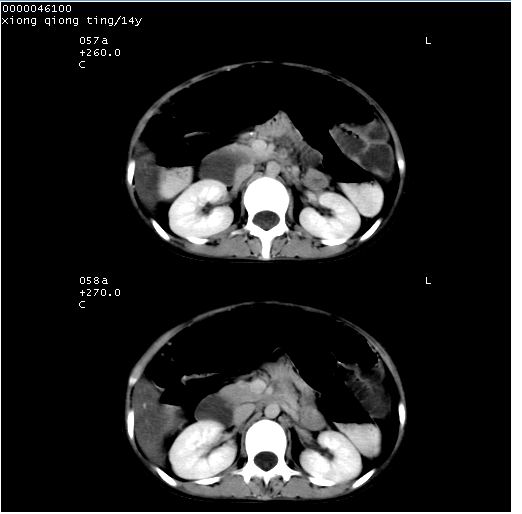

中下腹及盆腔ct轴位平扫+增强扫描(层厚10mm,螺距1.0,重建间隔10mm),图像如下:

(注:患儿检查当日上午9时口服胃肠道对比剂,下午3时许行ct扫描检查,未行对比剂直肠保留灌肠,检查当日患儿腹泻)

中下腹及盆腔ct轴位扫描(ps+ce)提示:腹部肠管明显充气扩张,并见数个不同宽度之气液平面;疑不全性肠梗阻或肠郁张。临床会诊考虑为患儿腹泻,肠郁张所致;后来未经特殊处理,患儿大便恢复正常,亦无腹胀。

临床出院诊断:1)结核性腹膜炎。2)腹膜后淋巴结结核。3)脂肪肝。